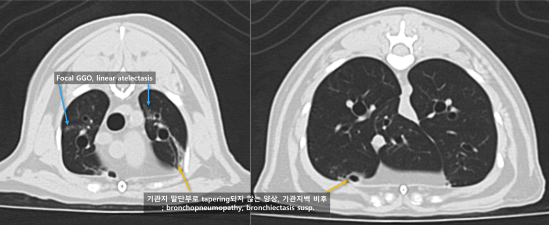

정확한 환자 상태 평가 및 확정진단을 위하여 전신 CT 촬영 및 조직 검사를 계획하였습니다.

고양이 구강 SCC 내원 당시 CT 검사 3 / 출처: 에스동물암센터

📌CT 검사 결과

이번 영상 검사에서 확인된 병변은 위턱뼈(상악)에서 시작된 병변일 가능성이 가장 높습니다. 뼈가 녹아내리는 모습(bone lysis)과 뼈 표면이 반응하는 소견(periosteal reaction)이 보여, 악성 종양일 가능성을 우선적으로 고려해야 합니다.

다만, 코(비강)에서 시작된 병변이 위턱뼈로 퍼진 것일 가능성도 완전히 배제할 수는 없습니다. 따라서 정확한 원인을 알기 위해서는 조직 검사가 필요합니다.